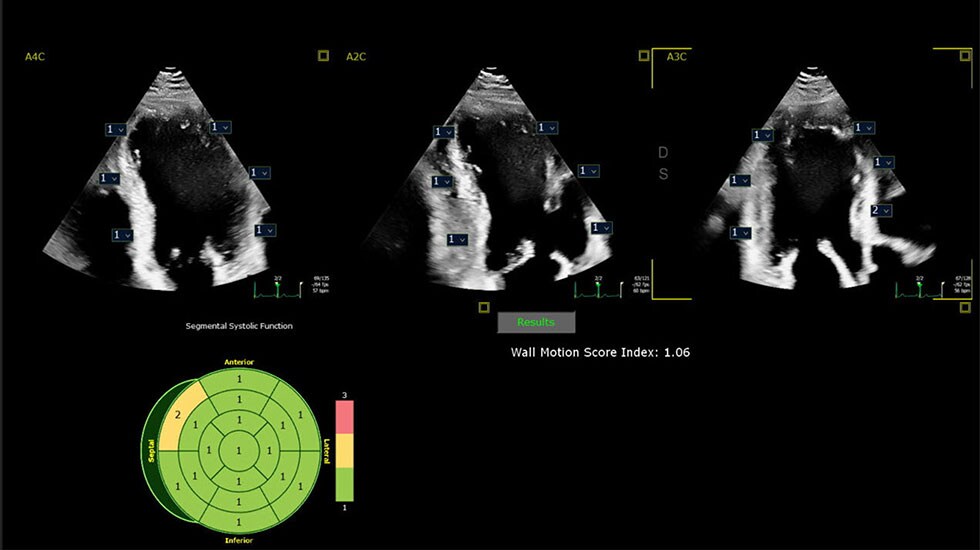

Millions of patients rely on cardiac ultrasound imaging for an initial assessment of a suspected heart condition before being referred for further examination. However, assessing a sequence of ultrasound images to detect abnormal movement of the heart walls – known as regional wall motion abnormalities (RWMA) – requires substantial experience. This process can also be time-consuming and often subjective in nature, potentially leading to significant user-to-user variability, especially when attempting to make quantitative assessments.

Internationally renowned cardiologist Dr. Roberto M. Lang and his team at the University of Chicago Medical Center (Chicago, US) investigated whether artificial intelligence (AI) could consistently identify RWMA and perform as well as expert echocardiographers when reading ultrasound images of the beating heart. To test their ideas, they developed an AI model to identify RWMA using divisions of the myocardial wall that are consistent with current ASE guidelines. The AI model was trained on an impressive dataset consisting of 15,746 clinical transthoracic echocardiography studies, with ground truth established by the corresponding clinical reports. The group then performed a comprehensive evaluation where the AI model went head-to-head against a group of clinical readers to evaluate RWMA in a test dataset unseen by either the AI model or the human readers, with ground truth for this test established by a separate panel of experts.

The results were astounding. Not only did the AI model perform the RWMA assessment in seconds, but its performance showed no statistical difference (defined as p < 0.05) as compared to the expert readers in the group. Moreover, the AI model demonstrated statistical superiority over a majority of novice readers to whom it was compared.